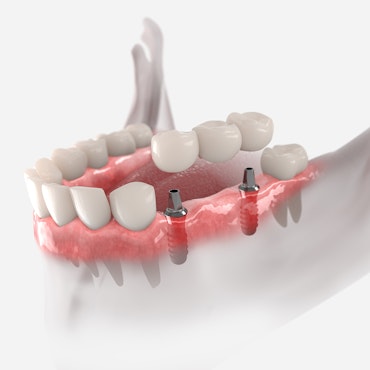

A smile has an incredible influence not only on how you are perceived by others, but how you perceive yourself. A healthy, beautiful mouth is much more than simply straight, white teeth. It involves a proper bite relationship (occlusion), joint and muscle comfort (TMJ), and proper soft tissue (gum) health. Our Vernon and Coventry, CT, dentists are dedicated to providing cosmetic dentistry and restorative procedures that can restore your smile to optimum health and appearance.

Our dentists accomplish this goal by developing individualized treatment plans based on your specific clinical needs and incorporating your own dental goals. This systemic approach involves exceptional care and time. If necessary, our dentists will work with the best specialists in the area to provide you the dental care you need.